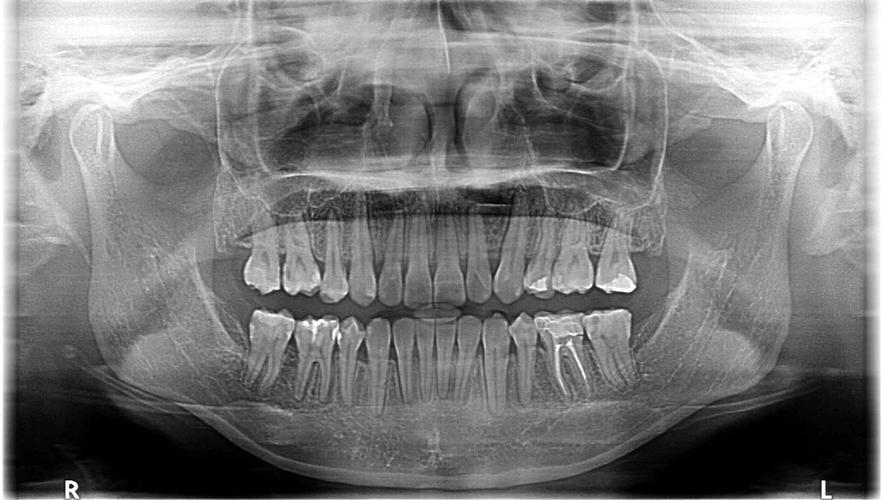

- 全景片标注示例:重点标注根尖阴影、牙槽骨吸收水平(用“箭头+文字”说明吸收程度,如“II度根尖周病变”)、牙齿萌出方向(用“曲线箭头”示意)。